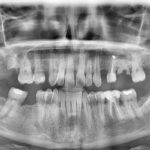

Paciente de 46 años acude a la consulta interesado en reponer las piezas ausentes.

En la primera visita se le diagnostica y presupuesta la exodoncia de restos radiculares en 17 y 26 y la realización de curetajes en ambas arcadas, así como la obturación de 2 caries proximales en 27 y 37.

También se le explica la necesidad de una fase ortodóncica previa a la reposición protésica de las piezas ausentes 14,24,26 y 46, cuyo objetivo es la alineación del sector anterior superior y la intrusión del mismo, especialmente del 23 y el cierre de los diastemas presentes, centrando la línea media y mejorando los espacios para la colocación de los respectivos implantes y sus correspondientes coronas.